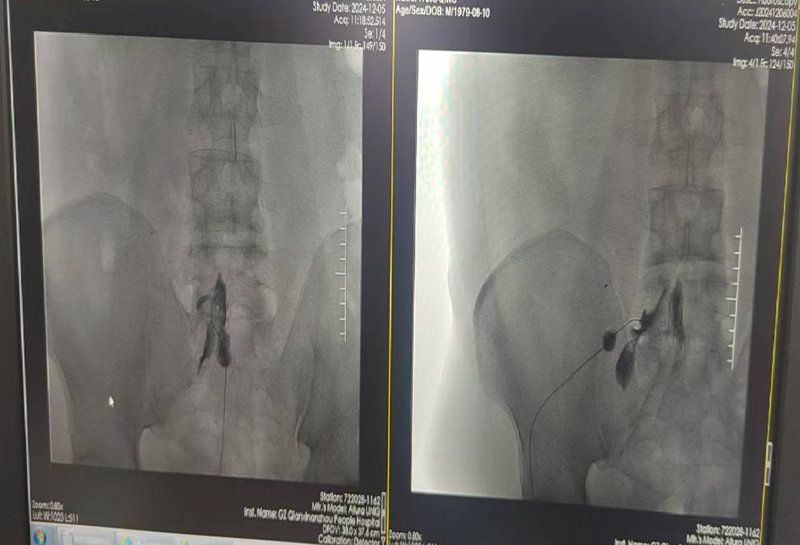

能完成该标准要求的绝大多数手术,包括选择性神经根阻滞技术、交感神经丛(干)介入医治技术、颅神经介入医治技术、神经射频调制技术、腰椎间盘介入医治技术、颈椎间盘介入医治技术、外周神经射频技术、脊髓电刺激、椎体成形术、硬膜外造影术、椎间盘造影术等。

交感神经丛(干)介入医治技术

硬膜外造影术